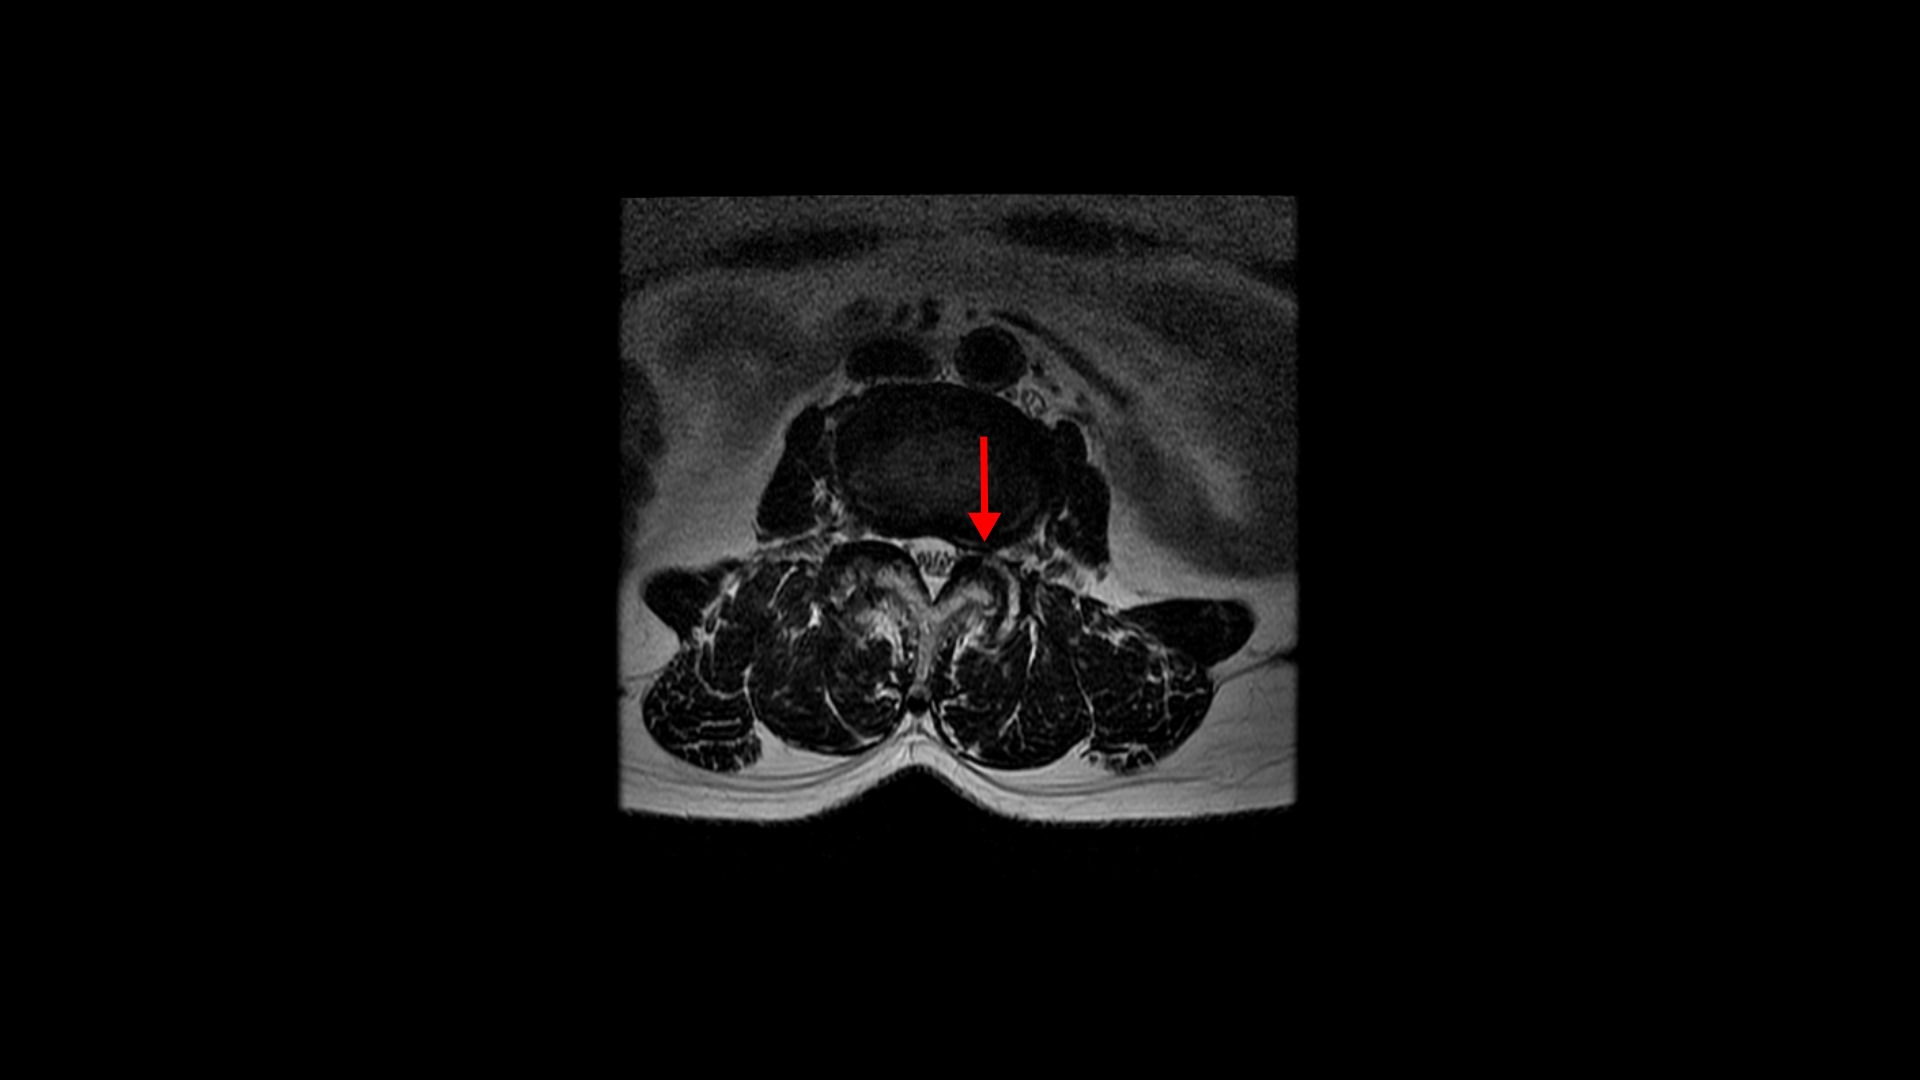

우선 이 환자분의 MRI를 함께 보겠습니다. 이 환자분의 척추에는 3번 4번과 4번 5번에 각각 1단계의 전방전위증이 있습니다.

중심성 협착도 있습니다.

그리고 중심성 협착도 있습니다.

그런데 이 환자분의 제일 불편한 증상은 왼쪽이 아니고 오른쪽 엉치와 다리 증상입니다. 이분 오른쪽 신경 구멍들을 보면 전부 다 넓게 잘 열려 있습니다.

엉치와 다리 방사통을 일으킬만한 특별한 신경 눌림이 보이지 않는 것입니다. 그럼에도 불구하고 여러 마디의 전방전위증과 척추관 협착 그리고 디스크 탈출이 있으니까 그것을 원인으로 보고 신경 주사도 맞고 시술도 받으셨습니다. 그러나 별 효과는 없었습니다. 그리고 대학병원에서도 결국은 수술밖에 방법이 없다고 수술을 권유하였습니다.